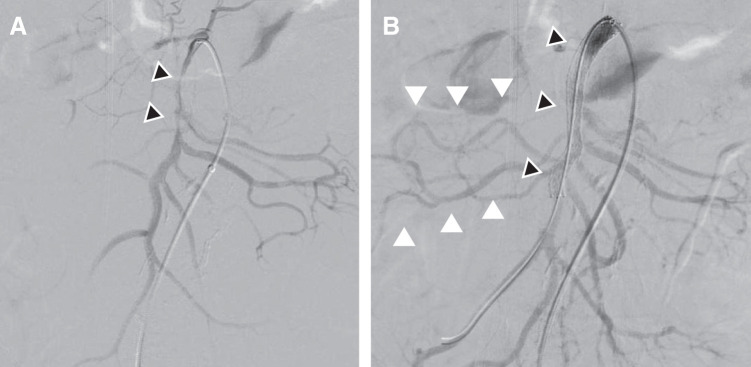

Case presentation: A 71-year-old male presented with acute chest pain and was diagnosed with Stanford Type A AAD extending to the abdominal aorta, with superior mesenteric artery (SMA) dissection leading to intestinal ischemia. To restore intestinal perfusion, emergency endovascular SMA stenting was performed as the initial intervention, followed by ascending aorta and total arch replacement using the frozen elephant trunk technique 12 hours later. The patient recovered without complications and was discharged ambulatory on postoperative day 20.